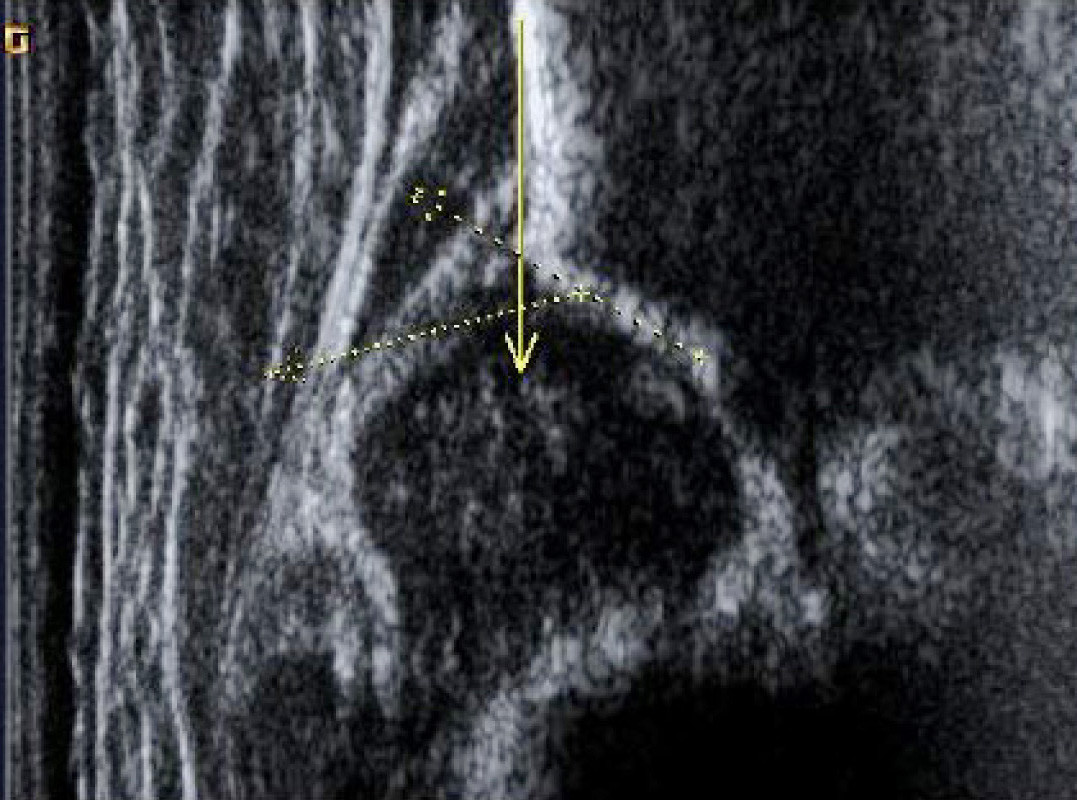

Sonographie der Säuglingshüfte

Sonographie der Säuglingshüfte wird durchgeführt